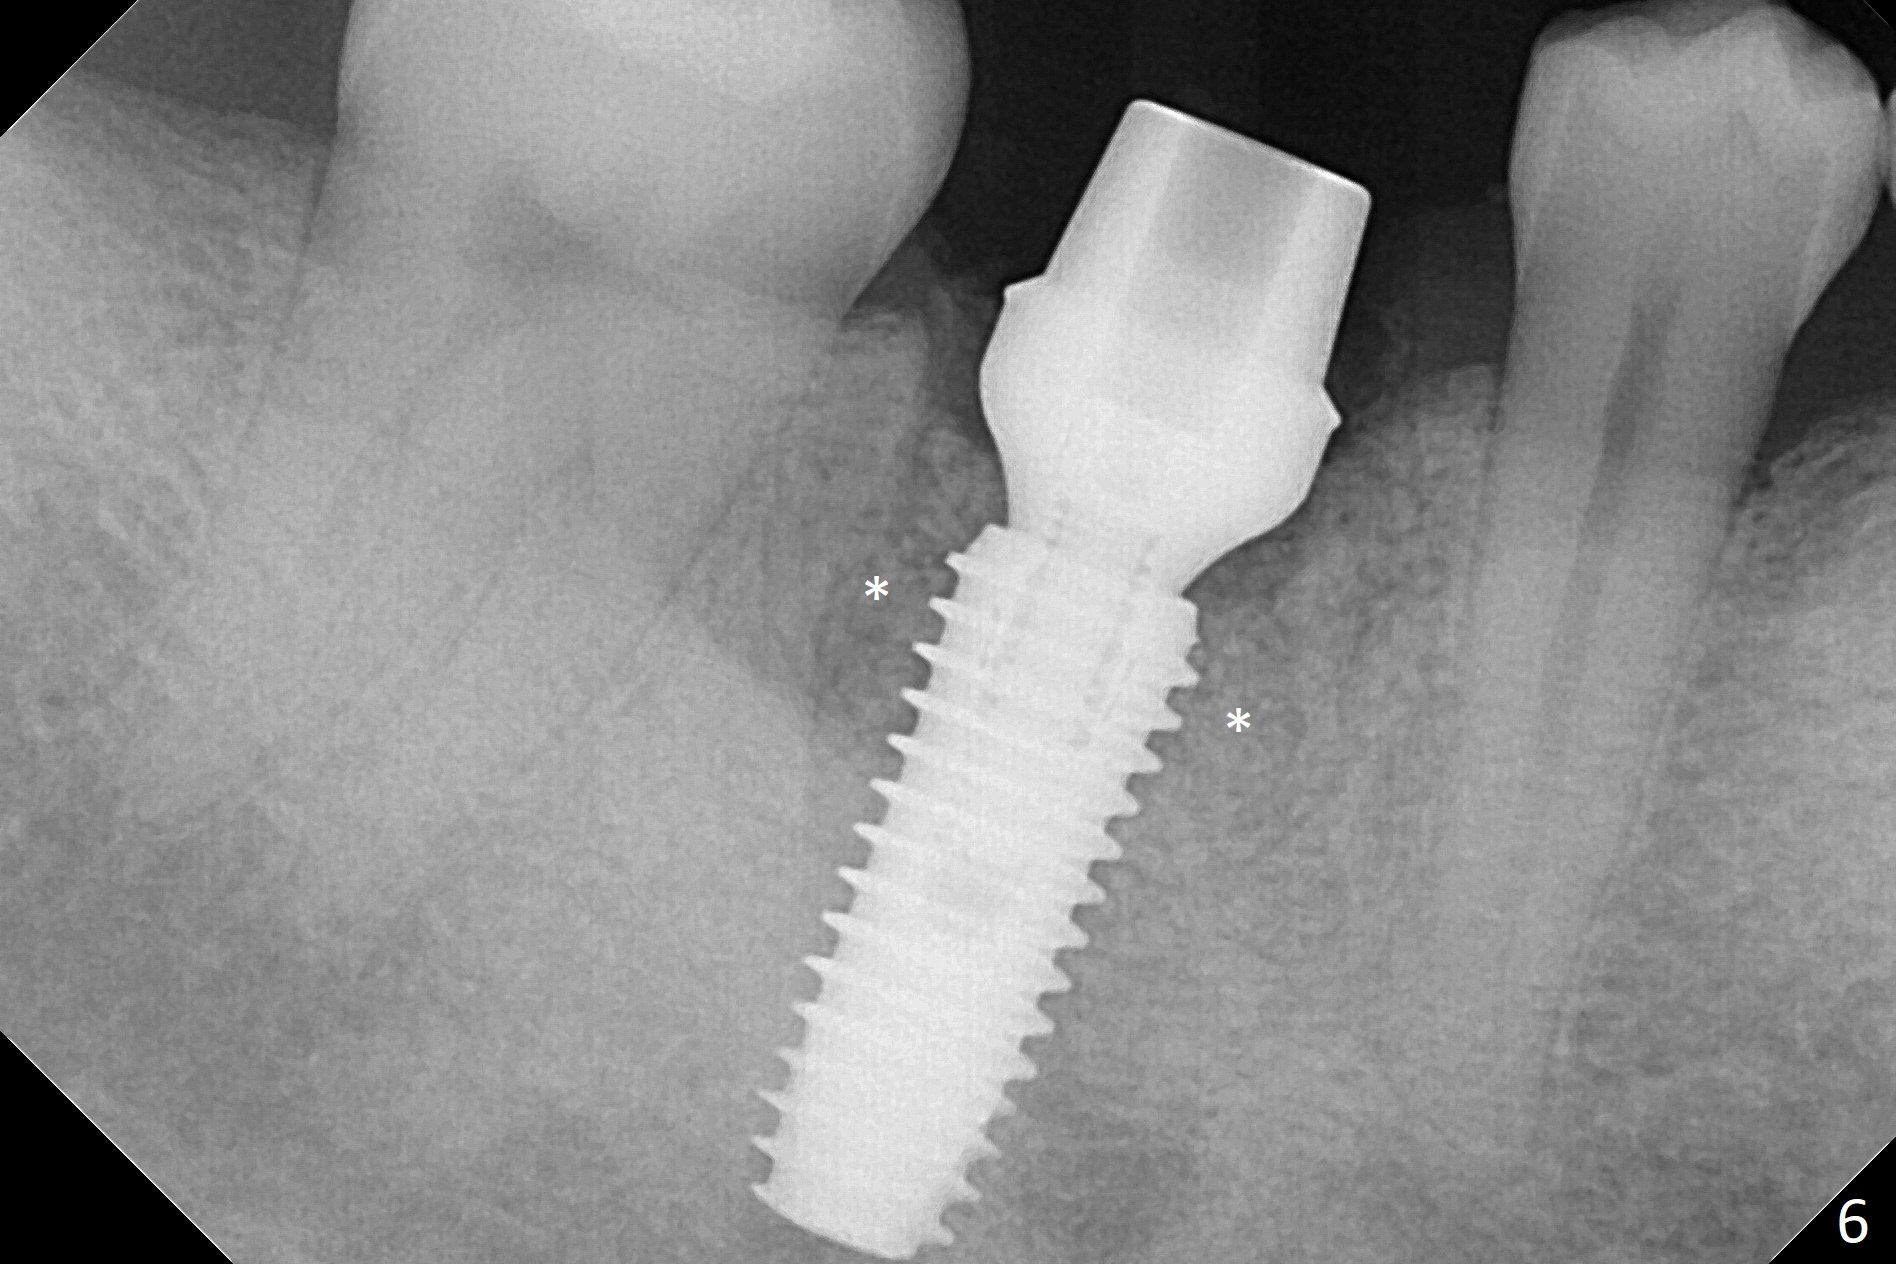

After the tooth #30 is extracted, the socket is 18 mm deep and the lingual plate is 4 mm tall. With hemorrhage, visibility of the socket, especially the bottom, is poor. The septum is almost completely defective. Following removal of the most buccal portion of the septum, osteotomy is initiated as buccal as possible, but it is mesial (Fig.1). In spite of effort to move the osteotomy distal, the osteotomy remains mesial and superficial (Fig.2 with 5 mm tap drill). Pain control is poor with infiltration. It appears that the smaller osteotomy (Fig.2 yellow line) may have extended close to the superior border of the Inferior Alveolar Canal (red line). It appears that there is 8.5 mm bone distal with ~ 2 mm clearance. After mandibular block, a new osteotomy is made distal; when a 3.8 mm drill is being used, there is hemorrhage from the osteotomy with apparent violation of the Canal integrity (Fig.3,4). But hemostasis is achieved with gauze pressure. A 5x13 mm implant is placed superficially (Fig.5) with a trace of the previous osteotomy (yellow line) and deep space created by the mesial osteotomy (*). Apparently the pathological and iatrogenic defects are filled with allograft (Fig.6 *). Guided surgery could have avoided the mesial osteotomy.

Fortunately no paresthesia is reported postop. Why is the Inferior Alveolar Canal not violated? Fig.7 is a coronal section of CBCT taken for a 40-year-old man at the lower 1st molar (at the septum). At the region, the Canal (brown circle) is close to the lingual plate (L). Because of severe bone loss of the lingual plate of this case (Fig.8 *), osteotomy is intentionally created buccal (green). The deep osteotomy may not contact the Canal, while the hemorrhage may stem from the medullary space (M in Fig.4,7). Bone morphology at the coronal end of the implant apparently changes 4 months postop, suggesting osteointegration (Fig.9). Impression is taken. Bone density around the implant at the crest seems to increase (Fig.10), while there is no soft tissue deficiency 10 months post cementation (Fig.11). The bone appears to regenerate toward the abutment, particularly distally, 14.5 months post cementation (Fig.12). Periimplantitis develops (bleeding on water pik and erythematous and tender buccal gingiva) 1 year 7 months post cementation (Fig.13,14). The 1st three threads are exposed (*). Bone graft with PRF and 6-month membrane or Cytoplast will be needed. Pain disappears 3 days of oral antibiotic. The gingiva looks healthy 1 month later when he returns for bone graft (Fig.15). But the lingual gingival cuff is not so healthy when the crown/abutment is removed (Fig.16 <). Bone graft is not done. For those patients with suboptimal oral hygiene, implants should be placed as low as possible, better with guide for precision.